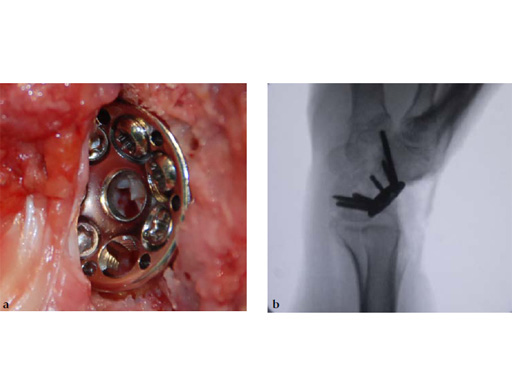

Fig 6ab Final appearance of fixed plate.

The 2.4 mm VA-locking intercarpal fusion system combines a circular plating technique with 2.4 mm variable angle locking technology and dedicated instrumentation . The circular plate design with a smooth surface and rounded edges minimizes soft-tissue irritation (Fig 2). To avoid impingement, proper positioning of the fusion as well as accurate placement and recession of the implant is mandatory. In addition to the standard reaming guide (Fig 3 in Instrument tab), the new reduction reaming guide permits reduction, compression and stabilization of the fusion site during the reaming procedure (Fig 4 in Instrument tab). Laser markings on the reamer support the surgeon by precisely controlling the depth of reaming for optimal countersinking of the plate (Fig 5 in Instrument tab).

The available two plate sizes include a 6-hole plate with a diameter of 15 mm, and a 7-hole plate with a diameter of 17 mm to fit different sized patients and applications.